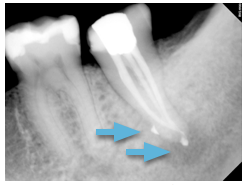

The patient returned for completion of the root canal 10 days after treatment was initiated. The post-op radiograph reveals sealer puffs along the lateral aspect of the root, which indicates a lateral canal was also filled. The core-buildup was placed and the patient was referred back to the referring general dentist for a full coverage crown.